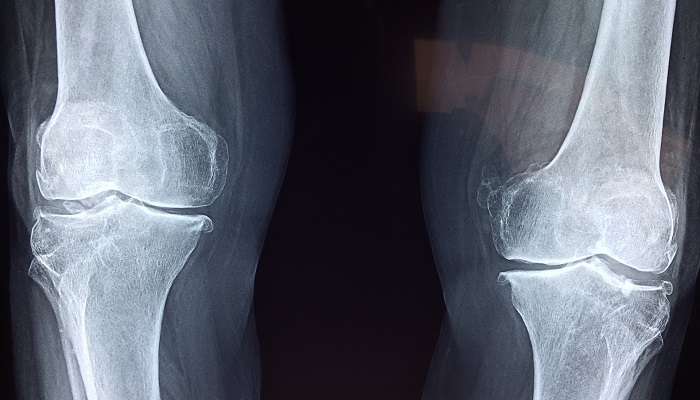

Knee pain is a common medical condition that affects everyone, irrespective of age. While the condition is often caused by arthritis among the elderly, it can result from many causes, with injury and overuse being the most common causes among most people.ย

In severe instances, knee pain can be debilitating and affect a personโs quality of life and mobility. If you have knee pains affecting your life or know someone with such a problem, it is essential to consider the available treatment options.

There are two main options when seeking treatment for your knee pain; surgical and non-surgical treatment. In most cases, a doctor may prescribe a surgical knee treatment where all other options may not be applicable. Some common types of treatment for knee pain without surgery worth looking at include: